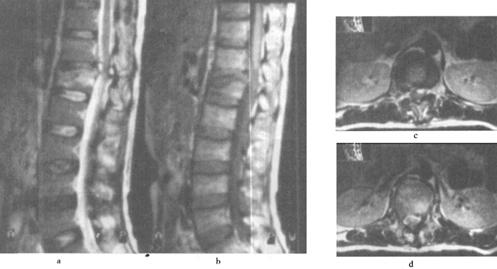

图7-15 颈髓挫裂伤:T1W(a)T2W(b)矢状面,脊髓增粒为髓水肿所致,T1W和T2W信号增高。横断面(c)脊髓内可见斑片状出血灶,硬膜外血肿T2W亦呈高信号,脊髓压迫向右后移位。颈后方软组织出血水肿,在T2W亦为高信号

图7-16 L1压缩骨折,脊髓挫裂伤:T1W(a)和T2W(b)矢状面,L1椎体呈楔状变形,椎体骨折,但无移位。后方硬膜外及脊髓内可见高信号血肿,在横断位T1W(c)、T2W(d)成像,如箭头所示脊髓圆锥内椭圆型高信号影,为出血所致。椎体骨髓水肿及出血。